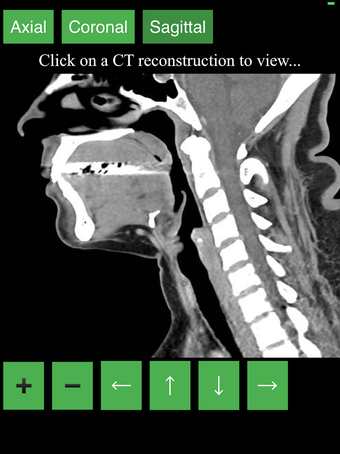

Aplikacja wyświetla przekrojowy obraz tomograficzny ciała człowieka i używa systemu kodowania kolorów, aby łatwo identyfikować różne struktury tkanek miękkich i kości. Może również być używana do badania określonej części ciała, takiej jak szyja, czaszka, obręcz barkowa lub klatka piersiowa.

Użytkownik może przesuwać obraz i powiększać go, aby lepiej zidentyfikować struktury i powiększyć obraz do dalszych badań.